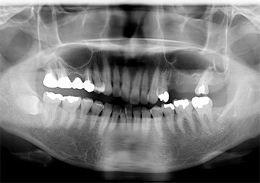

下顎のALL-ON-4①(下の歯のオールオンフォー)

- 主訴

- もともと入っているインプラントの周りが腫れ、残りの歯も動いているので力が入らない

- 治療内容

- 下顎右側に以前埋入したインプラントの撤去を行い、歯周病の進行が著しかった残存歯の抜歯を行うと同時にインプラントの埋入を行い、当日仮歯を装着した

- 治療費用

- 下顎ALL-ON-4:4,000,000円(税別)

- 治療期間

- 6ヶ月